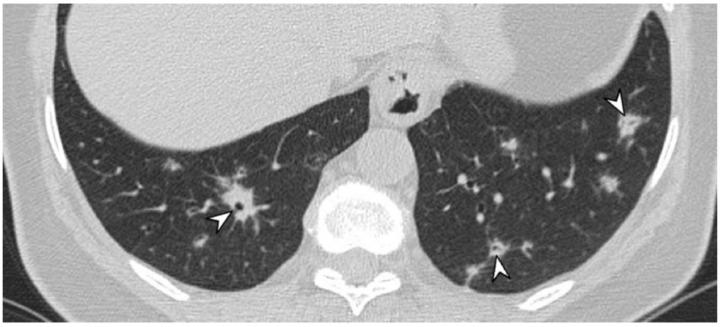

Vasculitides represent a heterogeneous group of immune-mediated disorders, characterized by a systemic inflammatory destructive process of the blood vessels resulting either in ischemia or hemorrhage. The organ involved and vessel size influence the pattern of presentation of the pathology. The lung is commonly involved in systemic vasculitides, with heterogeneous clinical, radiological, and histopathological presentations. Primary vasculitides most commonly associated with lung parenchymal involvement include small-vessel antineutrophil cytoplasmic autoantibody (ANCA)-associated vasculitides, such as granulomatosis with polyangiitis (GPA), eosinophilic granulomatosis with polyangiitis (EGPA), and microscopic polyangiitis (MPA). Several studies have reported cases of interstitial lung diseases (ILDs) associated with systemic vasculitis, particularly those positive for ANCA associated vasculitis/vasculitidis: AAV. We have selected from our case series different radiological features of pulmonary vasculitis (i.e., solitary or multiple nodules, cavitary lesions, nodules with centrilobular or peribronchial distribution, airspace consolidations, "crazy paving" appearance, interstitial disease), including cases with interstitial lung alterations. Therefore, the aim of this review is to describe the typical clinical manifestations of vasculitides and their main radiologic features (especially AAV).

血管炎是一组异质性的免疫介导性疾病,其特征是血管的系统性炎症性破坏过程,可导致缺血或出血。受累器官和血管大小会影响病理表现形式。肺部在系统性血管炎中常受累,临床表现、影像学表现和组织病理学表现各异。最常与肺实质受累相关的原发性血管炎包括小血管抗中性粒细胞胞浆自身抗体(ANCA)相关血管炎,如肉芽肿性多血管炎(GPA)、嗜酸性肉芽肿性多血管炎(EGPA)和显微镜下多血管炎(MPA)。多项研究报告了与系统性血管炎相关的间质性肺疾病(ILD)病例,尤其是那些ANCA相关血管炎/血管炎阳性的病例:AAV。我们从病例系列中选取了肺血管炎的不同放射学特征(即孤立或多发结节、空洞性病变、具有小叶中心或支气管周围分布的结节、气腔实变、“铺路石样”表现、间质性疾病),包括伴有间质性肺改变的病例。因此,本综述的目的是描述血管炎的典型临床表现及其主要放射学特征(尤其是AAV)。